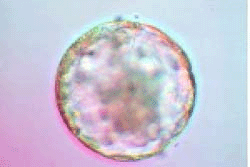

Это бластоциста. Похожа на тутовую ягоду?

Известно, что королеву делает хорошей ее окружение. Так и качество созревающей в организме женщины яйцеклетки зависит от множества факторов: это и различные внешние воздействия (температура, биохимический состав среды, клеточное окружение), и точное функционирование внутриклеточных механизмов, которые работают на сложном пути созревания яйцеклетки. Изначально стволовая половая клетка (предшественник яйцеклетки) носит в себе двойной набор хромосом, что свойственно всем остальным клеткам организма, и только претерпевая два редукционных деления (в которых происходит уменьшение числа хромосом в два раза), она становится настоящей половой клеткой - ооцитом. В течение этого периода созревающая яйцеклетка дважды останавливается в своем развитии (I и II блоки созревания), и "разбудить" ее могут только следующие события: I блок снимается пиком ЛГ, предшествующим овуляции, а II блок - в процессе оплодотворения. Если на этом уровне клеточной организации происходят какие-либо нарушения, то процесс созревания ооцита может остановиться на стадиях I или II блоков. Помимо процессов созревания ядерного аппарата, в самой цитоплазме яйцеклетки также происходят структурные и биохимические преобразования: идет активный синтез и накопление необходимых для развития ооцита и будущего эмбриона веществ - белков, молекул-источников энергии, молекул РНК, а также распределение по цитоплазме клеточных органелл. Например, митохондрии - "энергетические станции" клетки - распределяются в цитоплазме определенным образом, вследствие этого митохондриальная активность во всех участках цитоплазмы различна. Было показано, что существует прямая связь между увеличением возраста женщины и уменьшением митохондриальной активности в цитоплазме ооцитов и клетках эмбрионов. Следствием этого является снижение вероятности наступления беременности. Итак, зрелая яйцеклетка содержит в себе необходимый для развития эмбриона набор веществ и в момент овуляции находится на стадии II блока созревания, который снимается при оплодотворении сперматозоидом. Морфологическими признаками зрелой яйцеклетки являются наличие первого полярного тельца (образуется после снятия I блока созревания) и отсутствие клеточного ядра (зародышевого пузырька). Косвенным признаком степени зрелости ооцита может быть состояние кумулюса (оболочки, состоящей из части клеток, которые окружали и питали яйцеклетку, когда она росла). По ходу созревания яйцеклетки кумулюс становится более рыхлым, вязким.